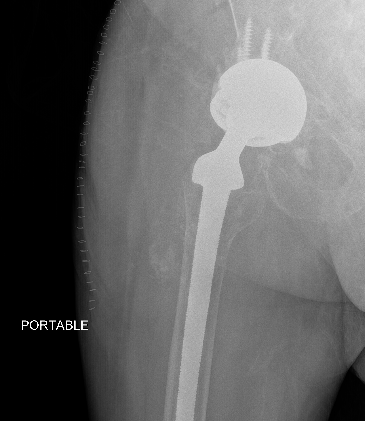

1. Acetabular Inclination

AP Xray

Excessive acetabular inclination